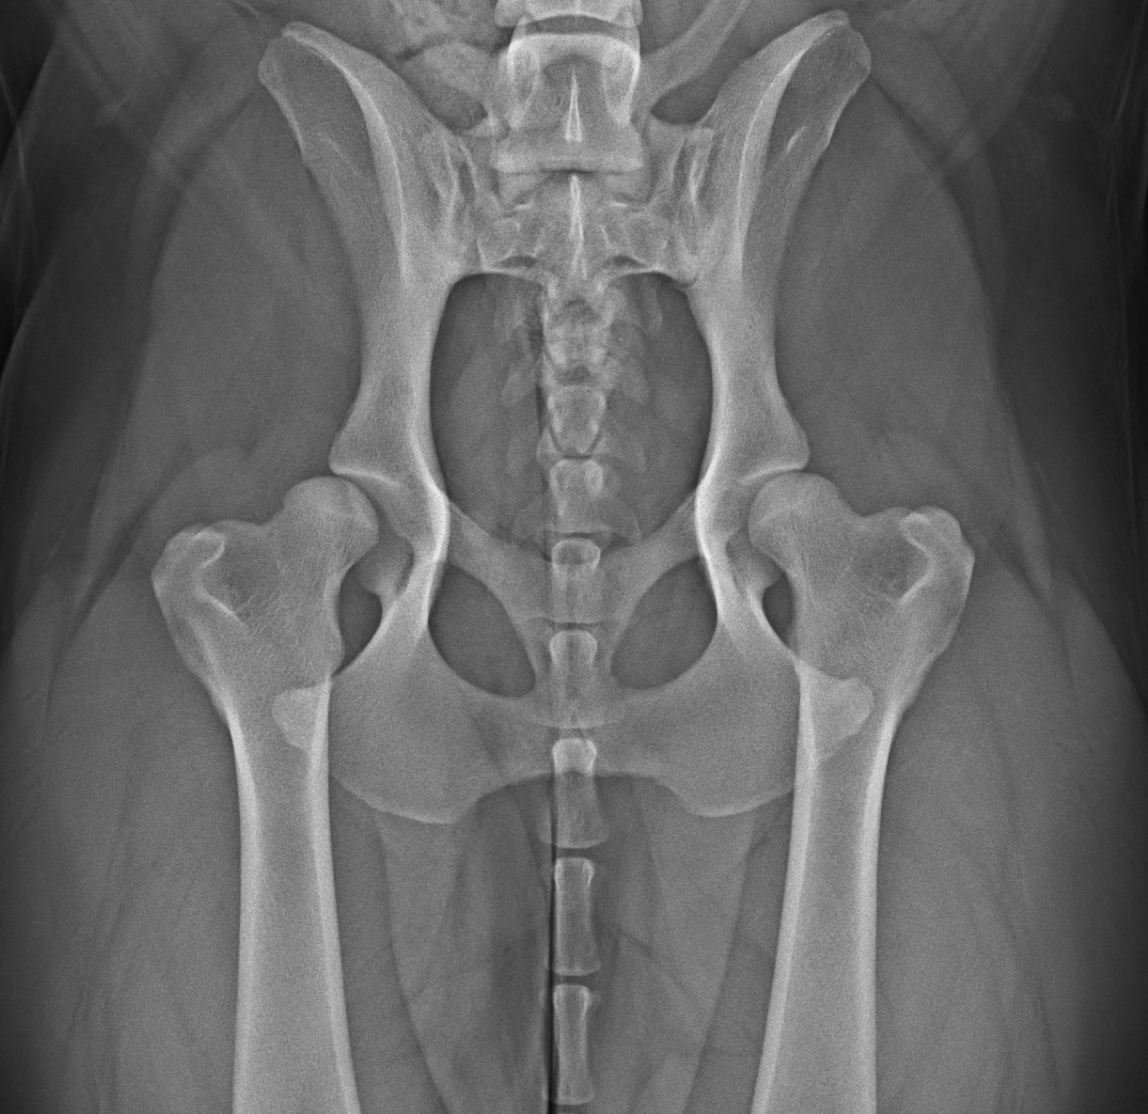

Radiografia di un bacino di un cane con displasia d'anca.

Studi radiografici per ricerca displasie

anche/gomiti (HD/ED)

Eseguo studi radiografici per valutare la presenza di displasia dell’anca e del gomito nel cane, seguendo protocolli di posizionamento per la certificazione Celemasche.

Nel corso dell’esame viene valutata la congruità articolare, eventuali segni di artrosi e caratteristiche anatomiche rilevanti, con misurazioni per la trascrizione ufficiale nel pedigree.